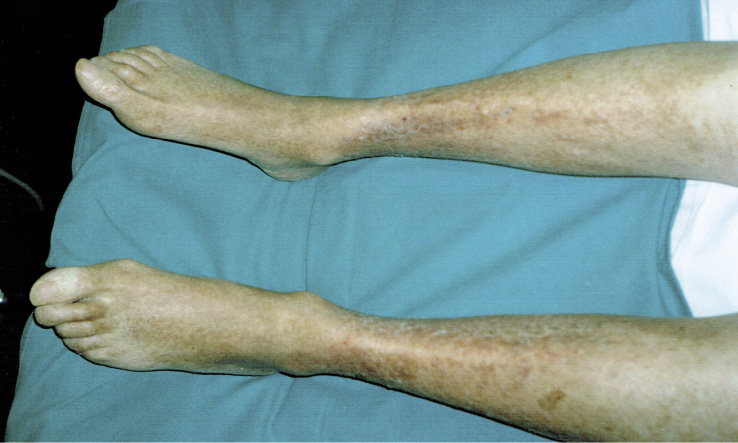

L’obiettività all’ingresso dimostrava: broncospasmo diffuso, edemi declivi, lieve stasi polmonare, cute delle gambe e dei piedi di color rosso “vinoso” (porpora cutanea accentuata dall’ortostatismo), chiazze purpuriche alla radice degli arti superiori e alle cosce (Figura 1).

Figura 1. Le gambe del paziente al momento della sua presentazione: cute di color rosso “vinoso” (porpora cutanea accentuata dall’ortostatismo)